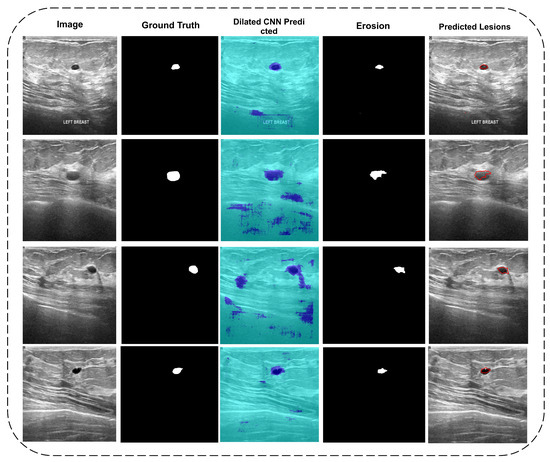

3.1. Segmentation

3.1.1. Dilated Semantic Convolutional Neural Network

3.1.2. Erosion

4.1. Di-CNN Evaluation